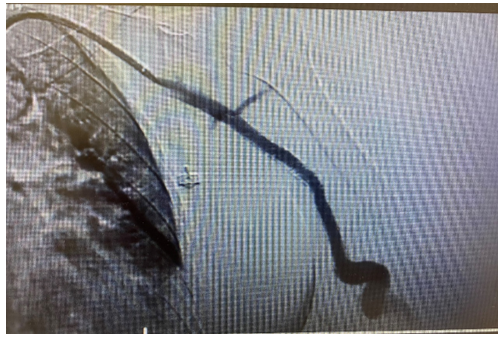

The patient was heparinized with a 5000UI intravenous bolus. The brachial artery was properly catheterized and we performed a thrombectomy with Indigo 8F, with a successful arterial recanalization followed by a proper angioplasty. After proper evaluation, we performed an implant of a Merit Wrapsody 8x125mm covered stent within the brachial artery and a concomitant resection of the venous segment and skin containing the cut-bruise wound + venous reconstruction. (Figures 3 and 4).

Figure 3: Intraoperative image central vein stenosis after successfully thrombetomy.